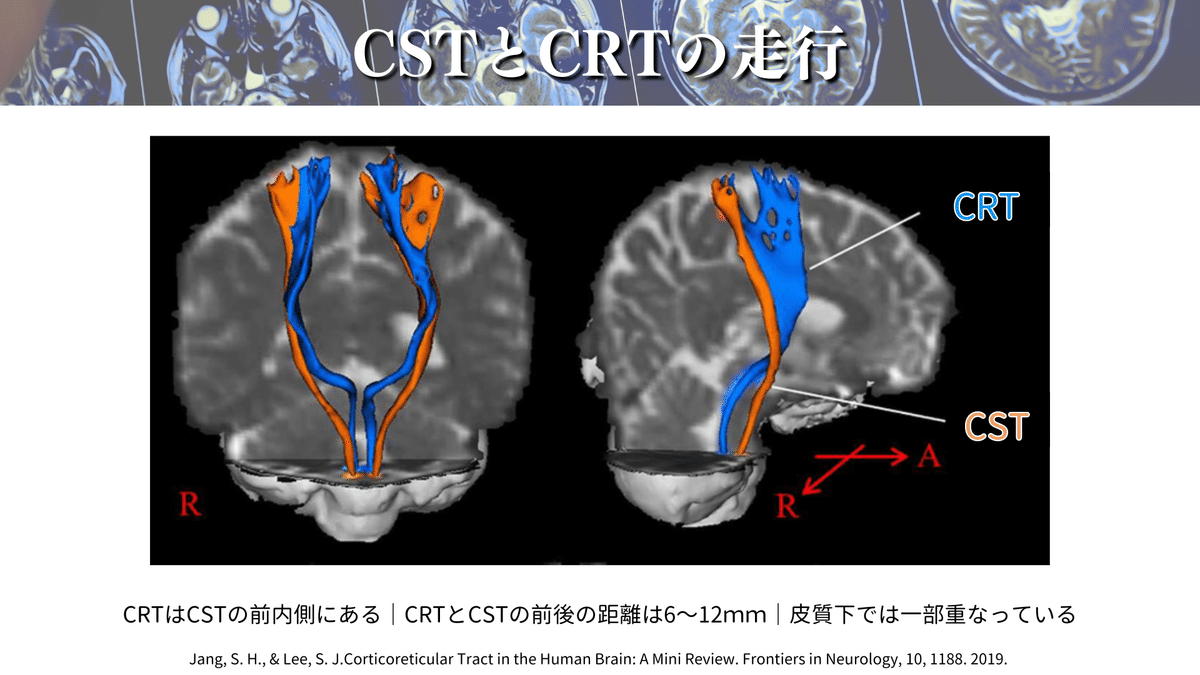

CSTの走行は養成校でも習っており、参考書でもよく取り上げられているのでイメージはついていました。一方で、CRTの詳細な走行を解説している参考書は少ないので、この論文に出会ったときに「これじゃん😳✨」と思ったからです!

さらにこの論文では、上図のように拡散テンソルトラクトグラフィー(DTT)を用いてこれらの経路を視覚的に確認できる点が魅力です😍

CSTとCRTの理解を深めることで、CVD後の運動障害の評価や介入、予後予測などに役立つかもしれませんね🫡